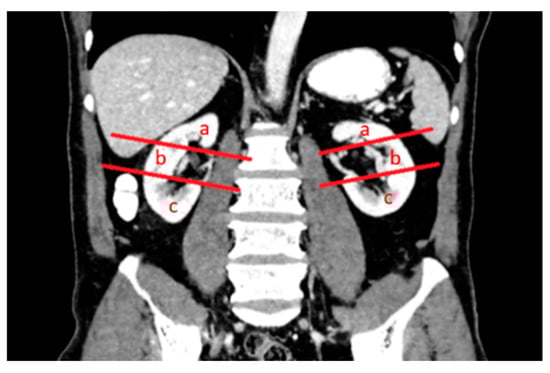

2.1. Percutaneous Microwave Ablation Therapy

2.3. Laparoscopic Ultrasound-Guided Percutaneous Microwave Ablation Therapy